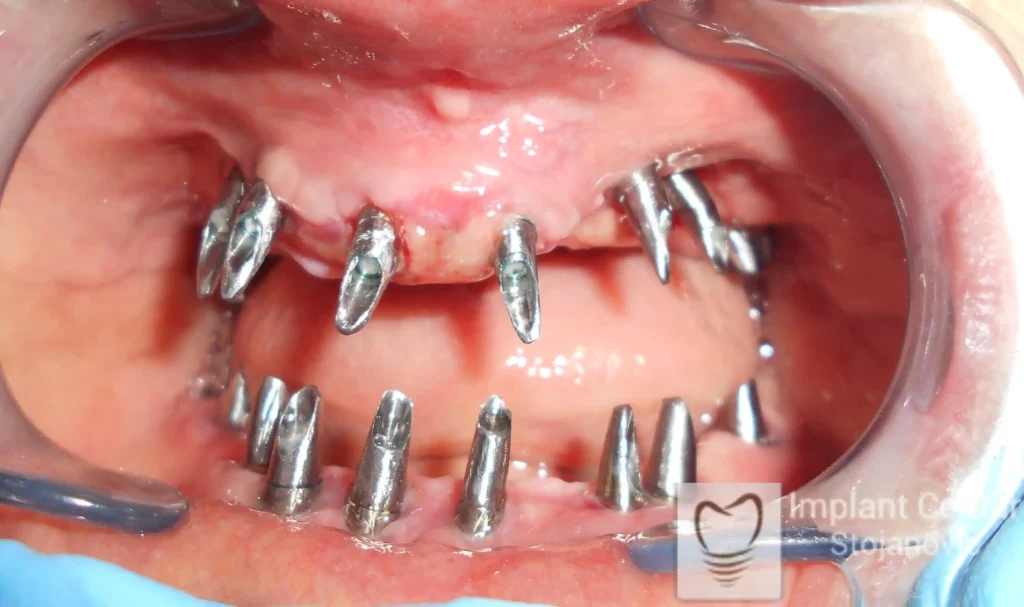

Pacijent sa rascepom usne, nepca i alveolarnog grebena uspešno je rehabilitovan fiksnim protetskim radom na implantatima. Pre dolaska u našu ordinaciju, pacijent je u gornjoj vilici nosio totalnu protezu preko preostalih zuba, dok je u donjoj vilici bio zbrinut parcijalnom mobilnom protezom. Tokom višegodišnje potrage za adekvatnim rešenjem, pacijent nije uspeo da pronađe zadovoljavajuću terapijsku opciju ni u zemlji ni u inostranstvu.

Nakon detaljnog kliničkog pregleda i analize radioloških snimaka, izrađen je sveobuhvatan plan terapije sa ciljem uklanjanja mobilnih proteza i postizanja maksimalne funkcionalne i estetske rehabilitacije. Zbog loše biološke vrednosti preostalih zuba, doneta je odluka o njihovom vađenju i ugradnji dentalnih implantata.

Poseban terapijski izazov predstavljalo je premošćavanje defekta nastalog usled rascepa, kao i ograničena količina raspoložive kosti u gornjoj vilici. Primenom većeg broja implantata i odgovarajućih procedura nadoknade kosti, postignuta je stabilna osnova za fiksni protetski rad.

Tokom perioda oseointegracije, pacijent je bio zbrinut fiksnim privremenim krunicama, čime je već pet dana nakon intervencije obezbeđena potpuna funkcionalna i estetska rehabilitacija. Nakon završetka perioda integracije implantata, izrađeni su definitivni cirkonijum-keramički mostovi na implantatima.